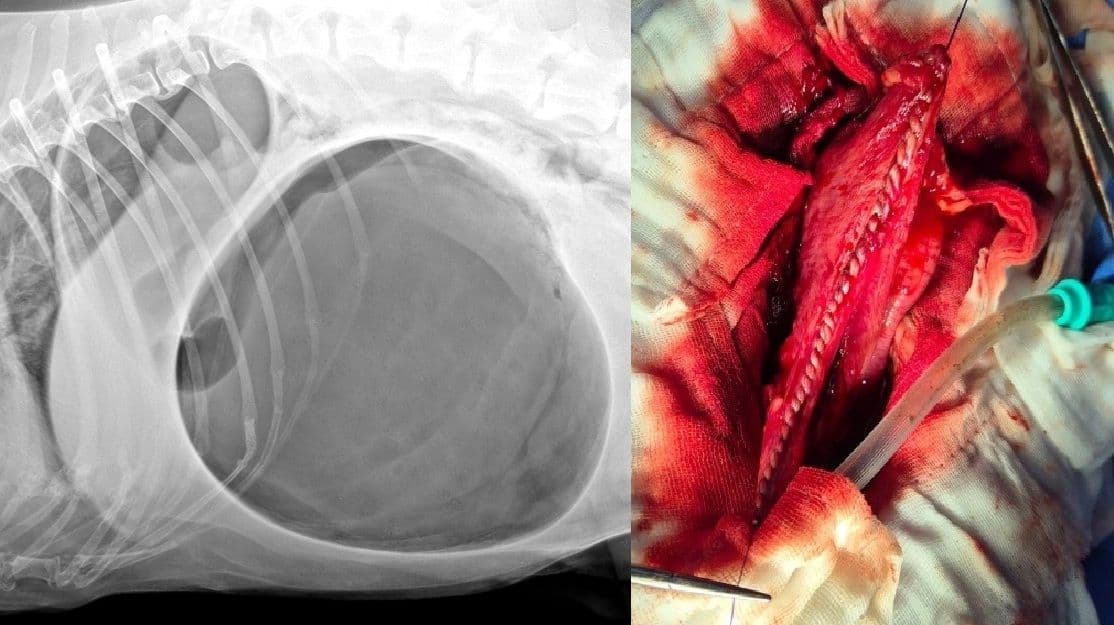

위확장염전 (GDV)

위가 꼬여 혈류가 차단되는 초응급 질환으로, 신속한 진단과 즉각적인 수술만이 생명을 구할 수 있습니다.